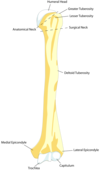

Label this diagram

Label this diagram of clavicle